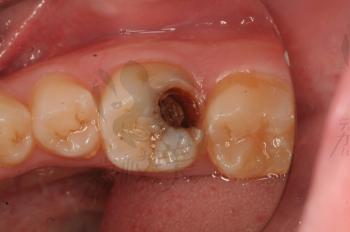

摘要:面對牙齒疼痛,特別是牙爛大窟窿帶來的困擾,需及時(shí)采取應(yīng)對措施。建議盡快就醫(yī),進(jìn)行專業(yè)牙齒檢查和治療。日常護(hù)理方面,注意口腔衛(wèi)生,定期刷牙,使用牙線和漱口水清潔口腔。飲食避免過冷過熱刺激,減少糖分?jǐn)z入,以防細(xì)菌滋生。如需緩解暫時(shí)疼痛,可服用止痛藥,但不可長期依賴。預(yù)防牙爛,定期口腔檢查至關(guān)重要。

牙齒疼痛是常見的口腔問題之一,而牙爛了個(gè)大窟窿晚上痛更是讓人難以忍受,這種情況不僅影響生活質(zhì)量,還可能引發(fā)其他口腔疾病,本文將為您解析牙爛窟窿的原因,并探討應(yīng)對方法和預(yù)防措施。

1、齲齒:齲齒是牙齒爛掉的主要原因之一,長期不注意口腔衛(wèi)生,細(xì)菌滋生導(dǎo)致牙齒逐漸腐蝕。

牙爛窟窿的治療

1、根管治療:對于牙爛窟窿較為嚴(yán)重的患者,根管治療是一種有效的治療方法,通過清除牙齒內(nèi)部的感染物質(zhì),進(jìn)行填充和修復(fù),以恢復(fù)牙齒功能。